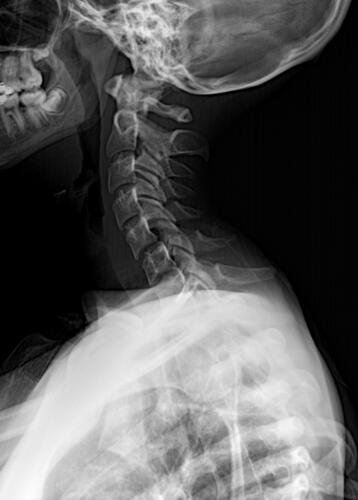

A Vá tem 13 anos e precisa urgentemente realizar uma cirurgia na coluna.Valentina foi surpreendida com o diagnóstico de escoliose hepática grave com 67 graus de desvio (desvio longitudinal da coluna), e precisa realizar com urgência a cirurgia corretiva, os exames foram realizados em Porto Alegre, mas a cirurgia está marcada para dia 13/07 em São Paulo devido a gravidade do caso, para isso a família terá que ficar residindo próximo ao hospital em São Paulo por no mínimo 30 dias para uma plena recuperação. Sabemos bem que qualquer procedimento cirúrgico é delicado, na coluna então nem se fala.Após o diagnóstico e o prognostico dessa doença a família se desfez de alguns bens (carro e moto) para cumprir os prazos dos exames e consultas, necessitando agora arrecadar o valor para a estadia da pequena Valentina e seu pós operatório (medicação, consultas e fisioterapia).

Em anexo os exames (laudo e imagens) para expressas a gravidade do caso.